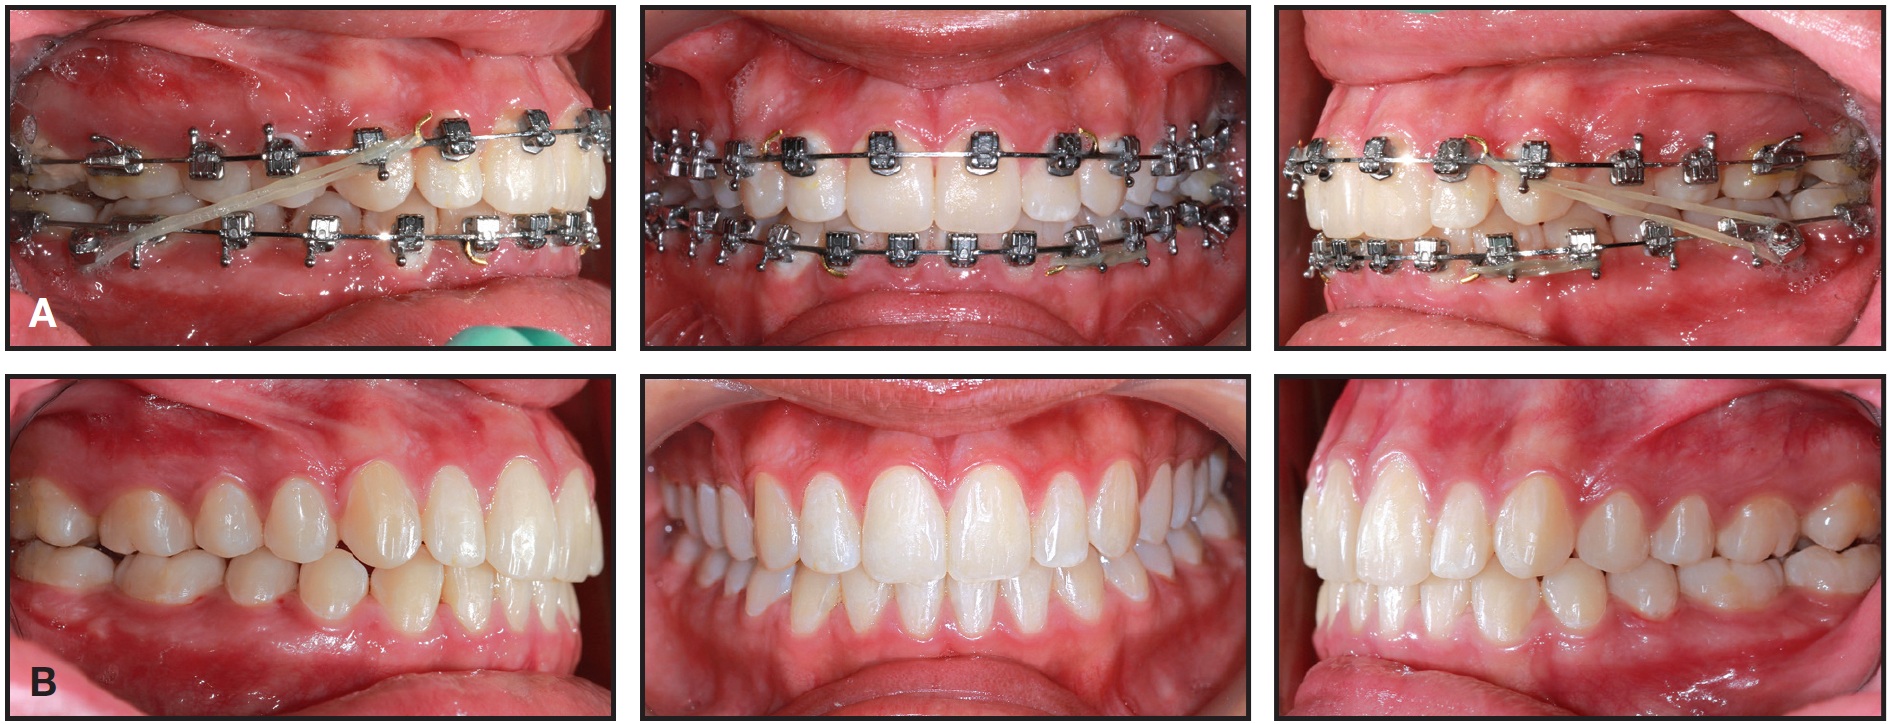

Fig. 5 Case 1. Comparison of pretreatment (A) and post treatment (B) photos, demonstrating improvements in smile arc, cant of upper occlusal plane, incisor and gingival display, and archform, with proper “white and pink” esthetic proportions.

Fig. 6 Case 1. Comparison of pre-treatment (A) and post-treatment (B) lateral cephalograms, showing slight clockwise rotation of maxillary occlusal plane with upper incisor extrusion in relation to stomion.

Case 6 exemplifies the standards of today’s smile esthetics, including proper dental and gingival display and a 12-tooth smile with a pleasing smile arc. Treatment with SAP bracket positioning and progressive case-management strategies also resulted in an improved occlusal plane in this patient (Figs. 25-29).

Fig. 25 Case 6. 21-year-old female patient with hypertrophic masseter muscles, Class III tendency, proclined upper incisors, and reverse curve smile arc before treatment. (Case images courtesy of Dr. Tomás Castellanos, Bogotá, Colombia.)

Fig. 26 Case 6. Treatment plan involved extracting third molars; injecting botulinum toxin in masseters one month prior to treatment; performing gingival recontouring and positive coronoplasty with composite resin; placing temporary anchorage devices in upper posterior buccal shelf; and engaging light, short Class III elastics at first appointment to distalize lower arch.

Fig. 27 Case 6. After nine months of treatment, showing maxillary anterior brackets bonded with SAP bracket positioning and inverted for additional crown torque (circled numbers).

Fig. 28 Case 6. A. After 12 months of treatment. B. After 15 months of treatment and gingival recontouring.

Fig. 29 Case 6. Comparison of photographs taken before treatment (A), after debonding (B), and after gingival recontouring (C), showing effectiveness of SAP bracket positioning and progressive case management strategies.